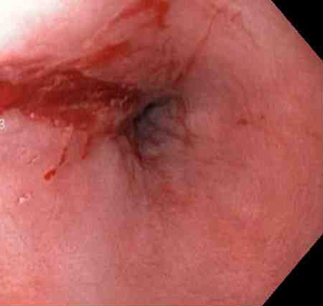

A terapia por injeção é comumente usada no tratamento da ulceração causadora de hemorragia digestiva alta, em combinação com terapia térmica ou mecânica. Seu papel no tratamento do sangramento por laceração de Mallory-Weiss foi estudado em uma pequena série.[71][72] Geralmente, o agente mais comumente usado é uma injeção de adrenalina; esse agente interrompe ou reduz a velocidade do sangramento por vasoconstrição ou tamponamento. É injetada ao redor ou dentro do ponto de sangramento. Agentes esclerosantes, como etanolamina e álcool, têm sido descritos na literatura; no entanto, eles são raramente usados na prática.[73][Figure caption and citation for the preceding image starts]: a laceração com sangramento ativo aparece como um defeito longitudinal vermelho com mucosa circundante normalDo acervo de Juan Carlos Munoz, MD, University of Florida [Citation ends].